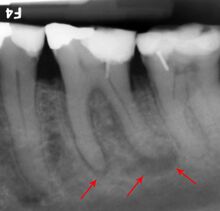

تقدير خطر الاضرار بالعصب

The inferior alveolar nerve (IAN), a branch of the trigeminal nerve (cranial nerve V), is a nerve that runs through the mandible (lower jaw) and supplies sensation to all the lower teeth, the lip and the chin. The lower teeth, and in particular the lower wisdom teeth, can therefore be in close proximity to this nerve. Damage to the inferior alveolar nerve is a risk of lower wisdom tooth removal (and other surgical procedures in the mandible).[16] This means there is a risk of temporary or permanent numbness or altered sensation to the lip +/- chin on the side the surgery is taking place. Therefore, in order to assess this risk and inform the patient, the position of the inferior alveolar nerve in relation to a lower wisdom tooth needs to be assessed radiographically prior to extraction.[16]

The proximity of the root to the canal can be assessed radiographically and there are several factors which can indicate high risk of nerve damage:[17]

- Darkening of the tooth root where it crosses the canal[17]

- Deviation of the canal[17]

- Narrowing of the roots[17]

- Loss of the lamina dura of the canal[17]

- Juxta apical area: a radiolucency associated with the root of the tooth which is not caused by periapical infection[17]